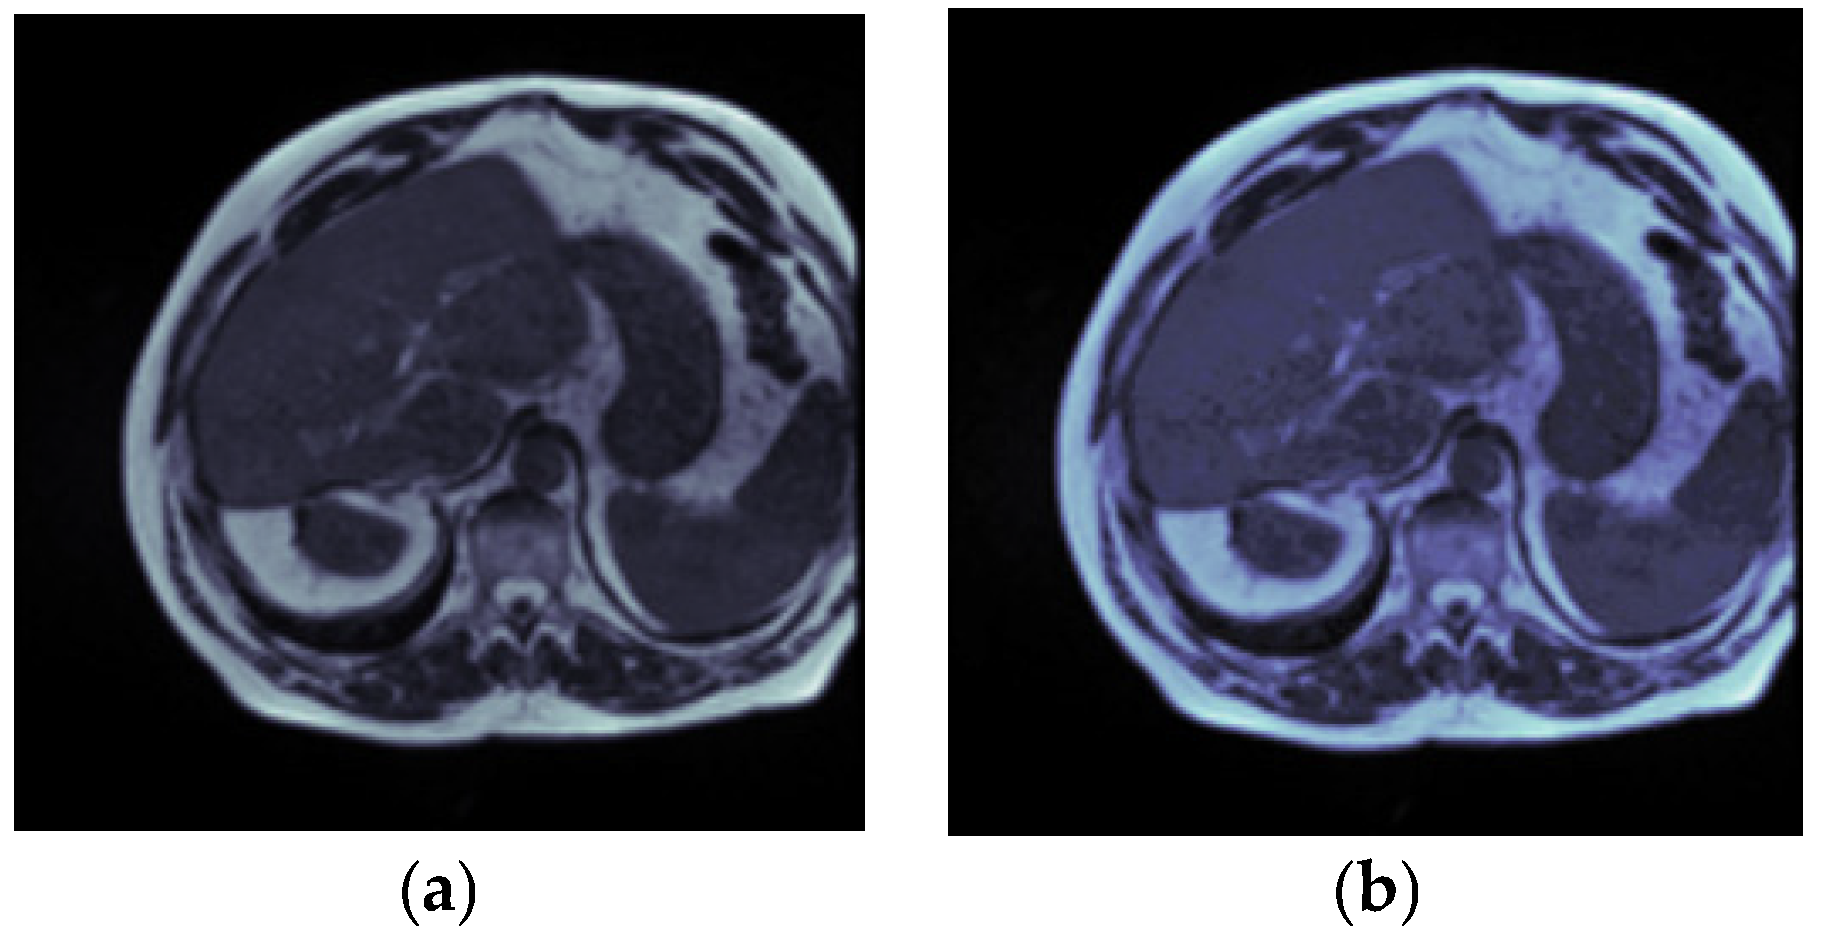

3.2. Dataset Pre-Processing

3.2.1. Resizing

3.2.2. Gaussian Filter

3.2.3. Normalization

3.2.4. Augmentation